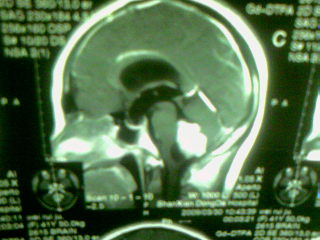

标题: MRI2125:女 45岁 头疼头晕3个月 [打印本页]

标题: MRI2125:女 45岁 头疼头晕3个月

1)考虑第四脑室脉络膜丛乳头状瘤,不排除室管膜瘤。2)阻塞性脑积水。

考虑 第四脑室室管膜瘤或脉络膜丛乳头状瘤伴梗阻性脑积水。

1)考虑第四脑室室管膜瘤,不排除脉络膜丛乳头状瘤。2)阻塞性脑积水。

第四脑室脉络丛乳头状瘤,典型!

考虑第四脑室室管膜瘤,不排除脉络膜丛乳头状瘤。2)阻塞性脑积水